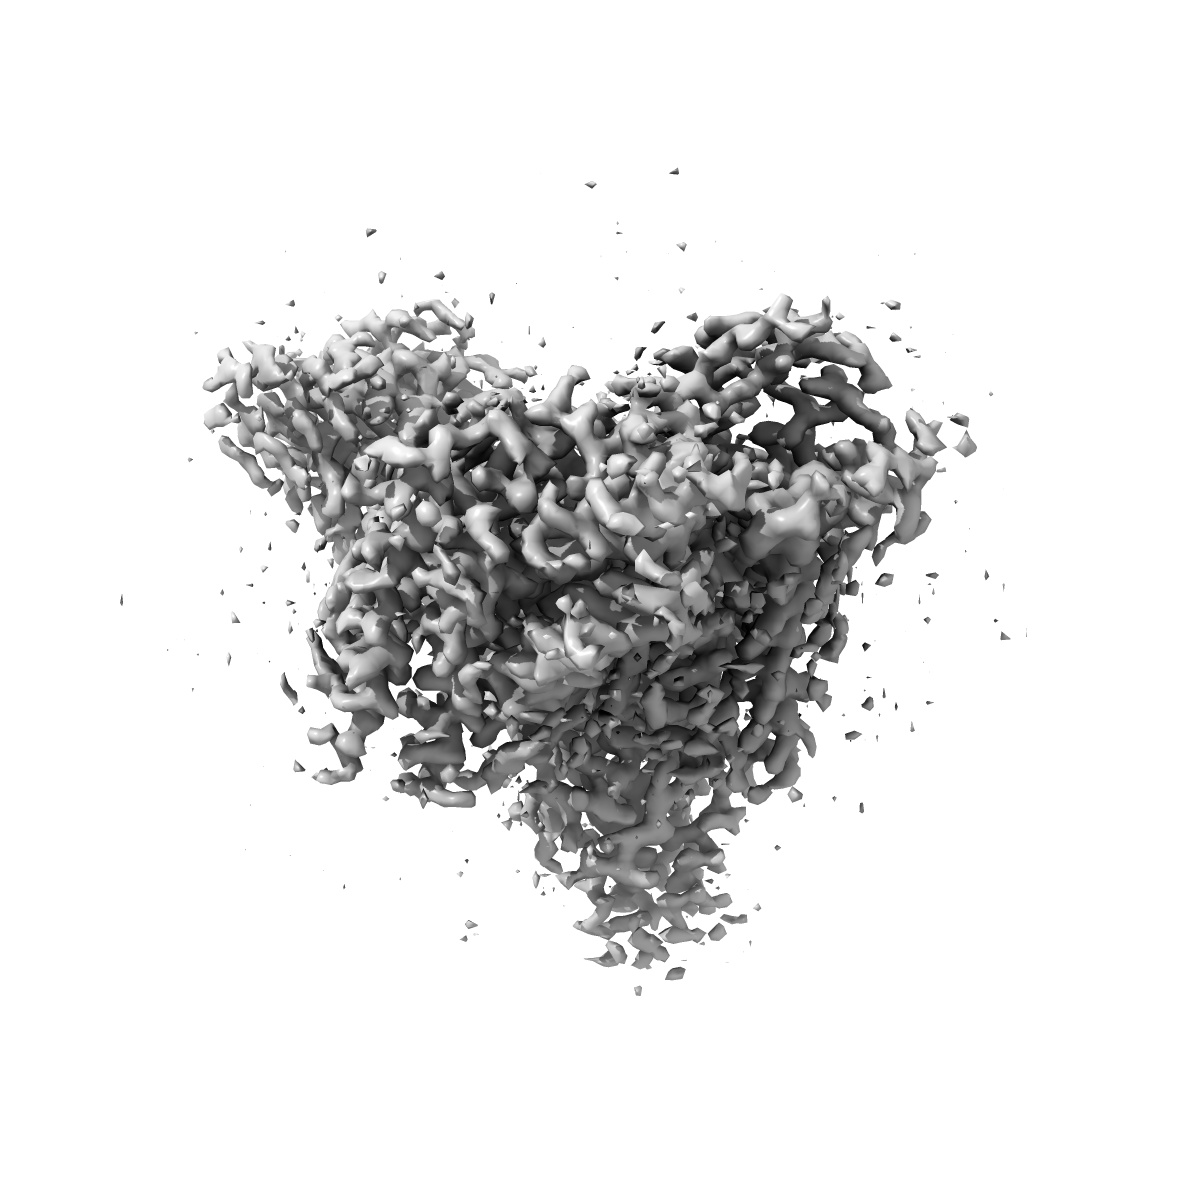

EMD-28069

Morphine-bound mu-opioid receptor-Gi complex

Single-particle3.2 Å

Sample: fentanyl bound mu-opioid receptor-G protein complex